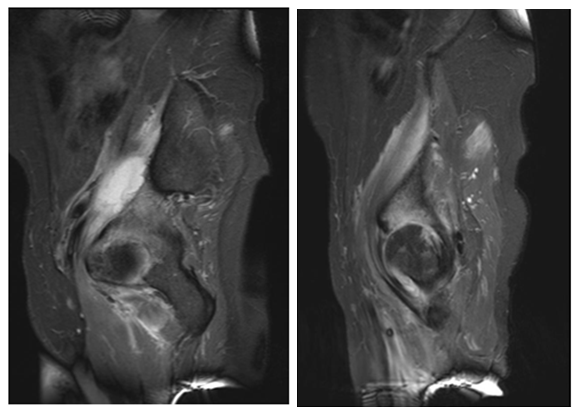

The second case is a 42 year old male patient who had a psoas muscle tear while playing football 3 weeks before consultation that complicated with psoas infection and bad response to antibiotics. MRI showed a clear collection in iliac fossa and advanced articular damage associated to synovitis.

Two stage treatments consisted in an initial surgery through a posterior approach, debridement of inflammatory tissues, neck osteotomy and acetabular reaming adding a temporal non-articulated antibiotic impregnated cement spacer for the resected femoral head. 6 weeks after surgery when intravenous antibiotic treatment was completed and laboratory inflammatory parameters were controlled, a second stage surgery was planified: Conversion to a hybrid arthroplasty for the first case and a non cemented total hip arthroplasty for the second case (Figure 1) (Figure 2).

Figure 2: 44 year male patient. A and B images show hip articular damage, C, D, E, F MRI shows a purulent collection and articular effusion. G image of the spacer H and I postoperative x-ray showing the non cemented total hip arthroplasty. Differed anatomy showed chronic inflammation compatible with osteomielitis for both cases, staphylococcus aureus meticilin resistant organism was isolated. Harris Hip Score of 96 at 2 year follow up, infection markers controlled, and no complications were reported.